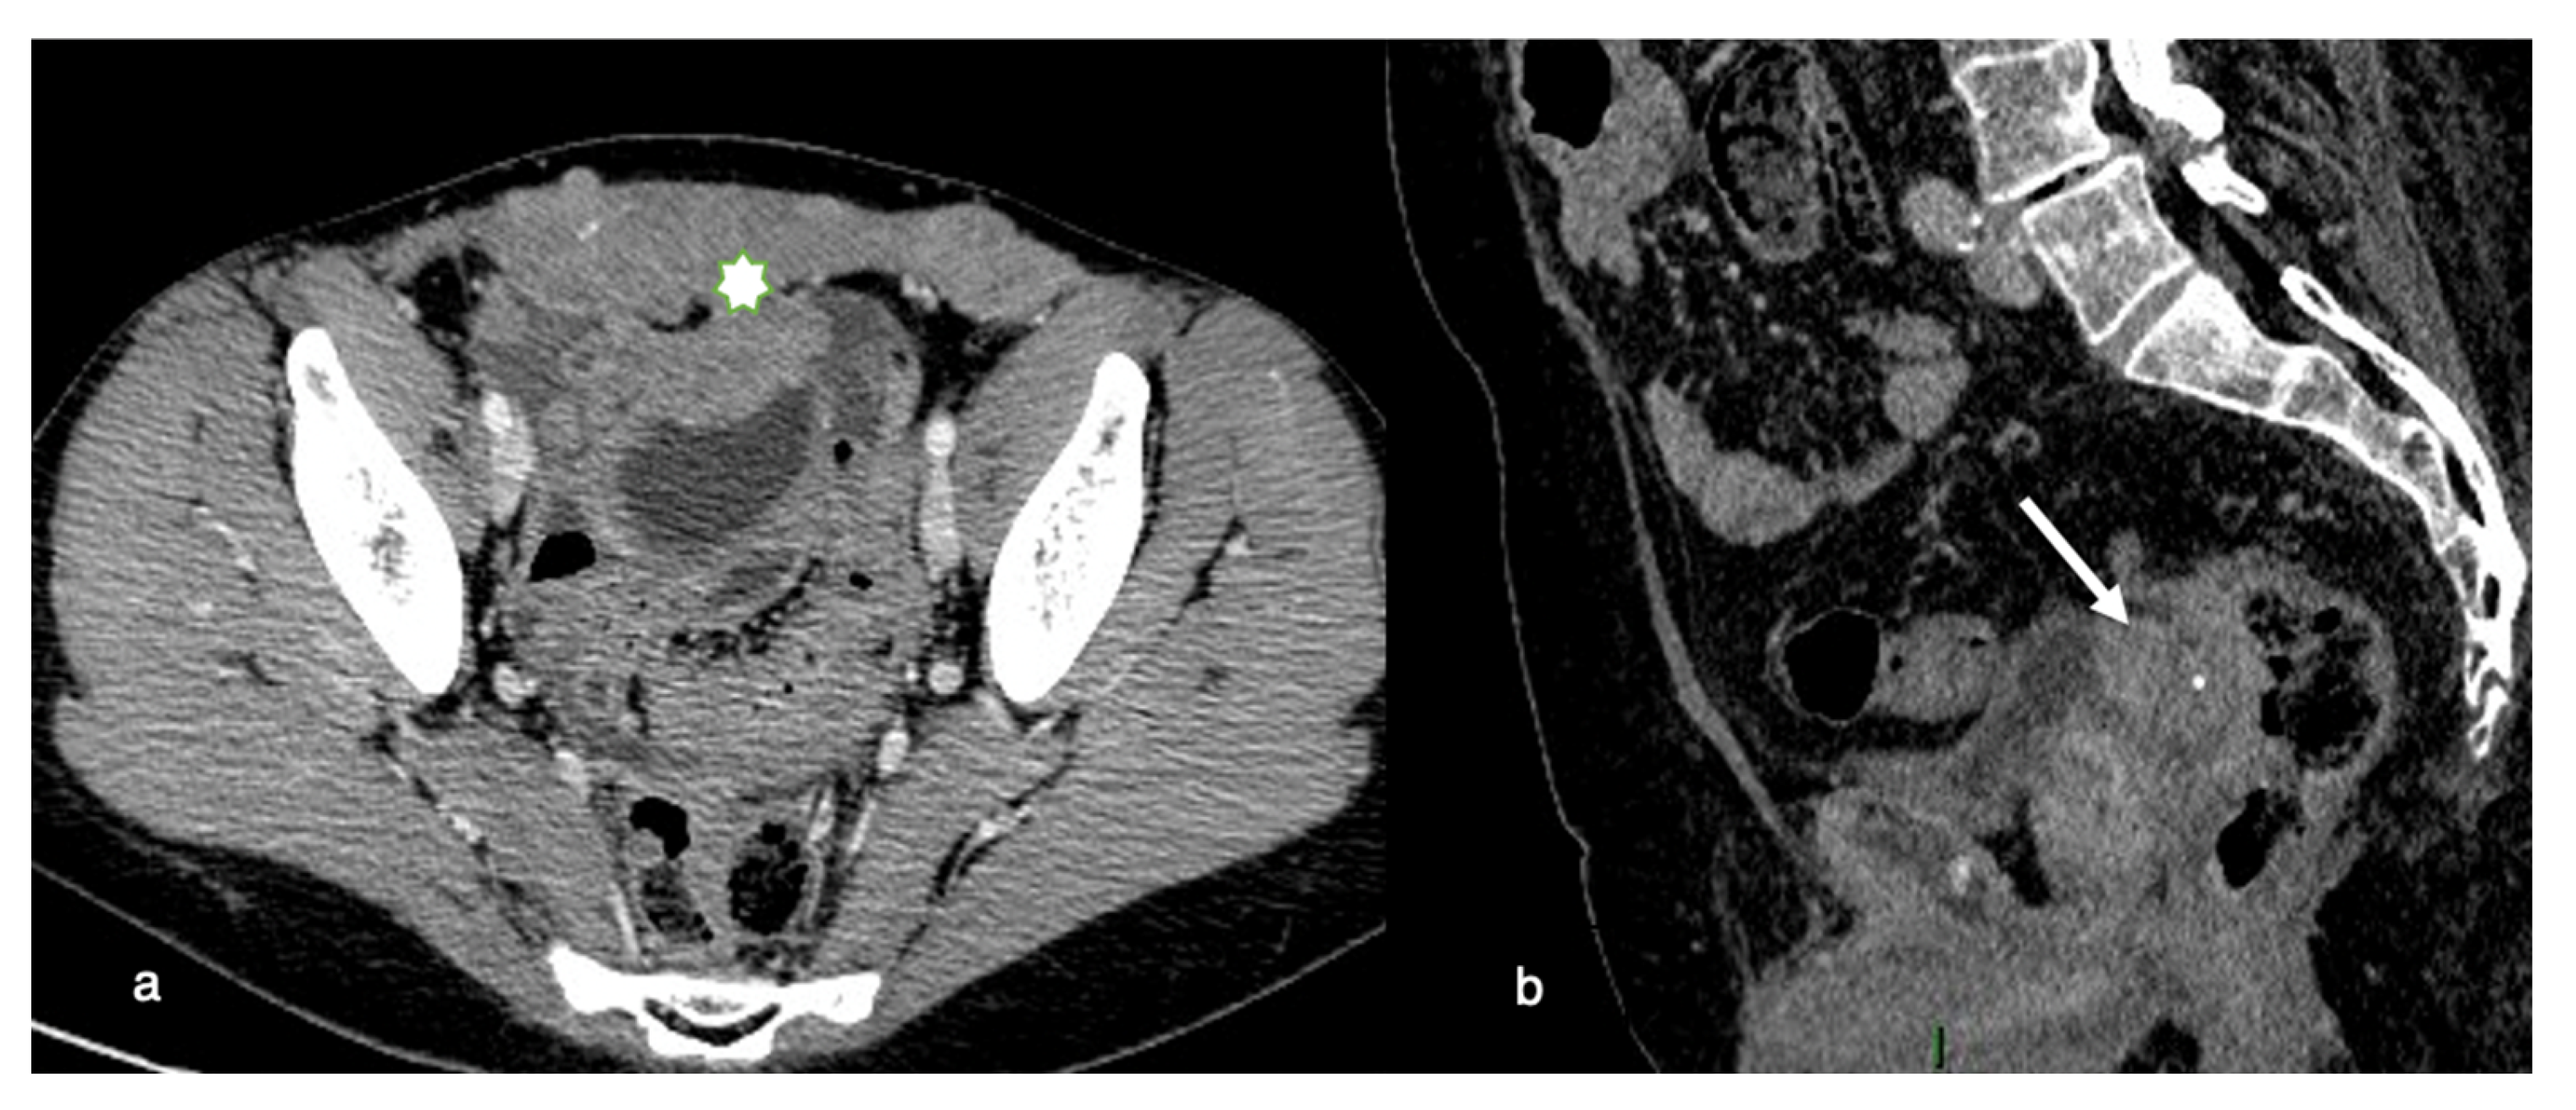

Invasive disease in the pelvis has significant implications for optimal resection. If the primary tumor is within 3 mm of the pelvic sidewall or surrounds more than 90% of the diameter of the iliac arteries with a vascular encasement, invasion of the pelvic wall may be assumed. Total cytoreduction can also be hampered by evidence of bladder trigone invasion (Figure 2).

Figure 2. Pelvic involvement. (a) Axial contrast-enhanced CT image shows a diffuse and irregular thickening of the anterior pelvic wall (asterisk) caused by the extension of tumoral tissue to adjacent muscles with penetration into the abdominal wall (b) Sagittal contrast-enhanced CT image shows a nodular cancerous implant located in the recto-sigmoid pouch (arrow) invading the bladder posterior wall (trigone of the bladder).